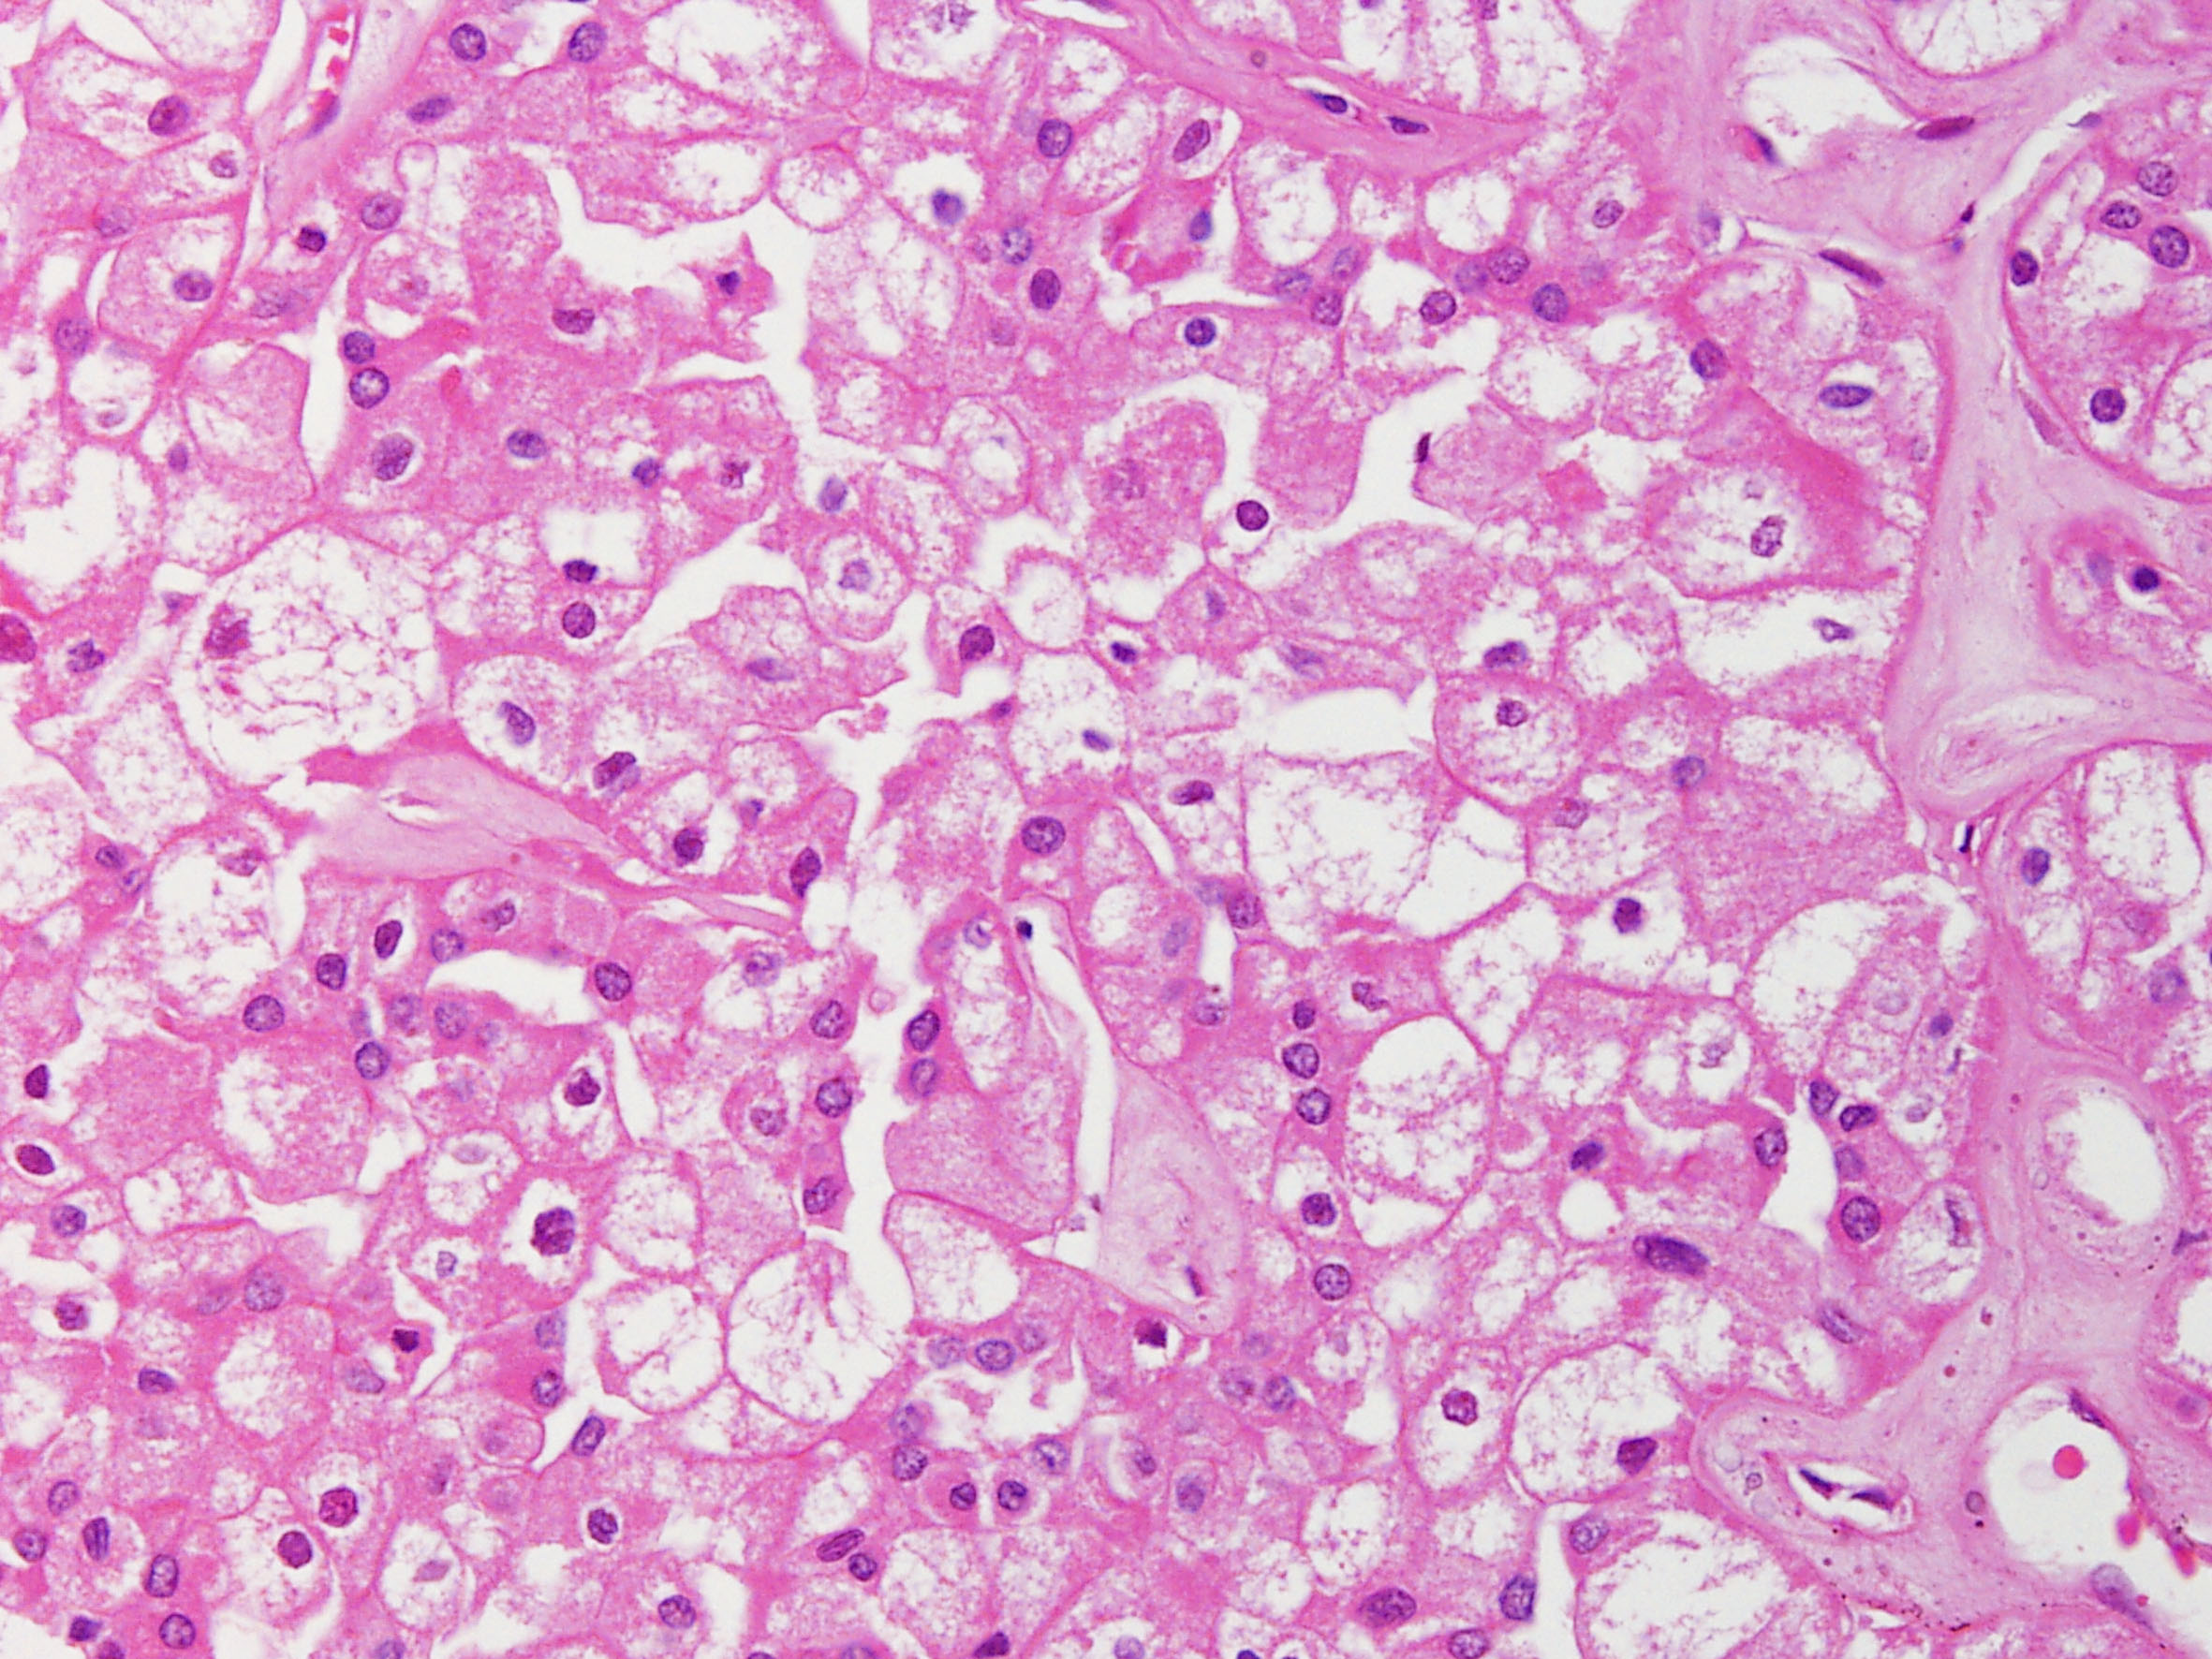

Chromophobe renal cell carcinoma